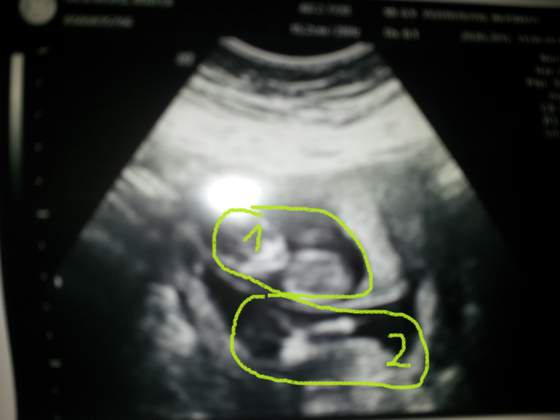

dzidzia gorna Zobacz załącznik 471626 i dolna Zobacz załącznik 471628